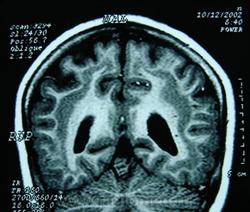

ГМ. Гетеротопии 1. Синдром «двойной коры» (Duplo córtex). +

Гетеротопии. Синдром «двойной коры» (Duplo córtex).

Наиболее частым вариантом миграционных нарушений является гетеротопия - скопление нейронов, остановившихся в различных аномальных местах на пути следования к коре головного мозга. Такая остановка происходит не позже 5-го месяца внутриутробного развития. Изолированный участок узловатой массы называется «гетеротопион». В настоящее время описаны следующие варианты гетеротопии:

- субэпендимальная нодулярная (узелковая) гетеротопия;

- ленточная (слоистая, ламинарная) гетеротопия;

- изолированная (одиночная) гетеротопия;

- синдром «двойной коры».